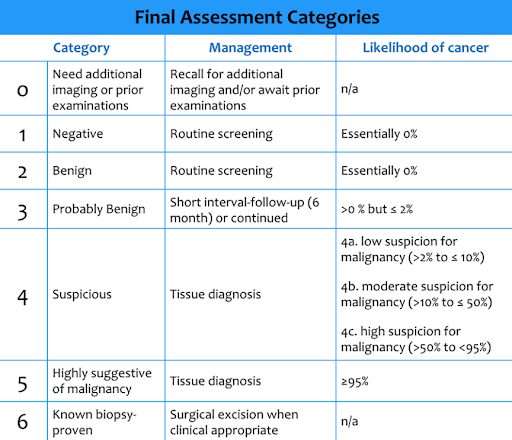

The US Preventive Services Task Force emphasizes the importance of mammography screening for women aged 50 to 74, recommending biennial screening. For women aged 40 to 49, the decision to begin biennial screening should be an individual one, considering the patient’s values, preferences, and health history. Mammograms utilize The Breast Imaging Reporting and Data System (BI-RADS) classification which ranges from 0 (Incomplete: Need Additional Imaging Evaluation) to 6 (Known Biopsy-Proven Malignancy), helping to classify a patient’s risk of breast cancer and recommend appropriate follow-up actions.

While the USPSTF does not specifically recommend routine ultrasound screening for breast cancer, it is often used as an adjunctive tool, especially in women with dense breast tissue where mammography’s sensitivity may be reduced. The sensitivity for breast cancer detection using both mammography and ultrasound increases to 97.3% (Berg 2020).